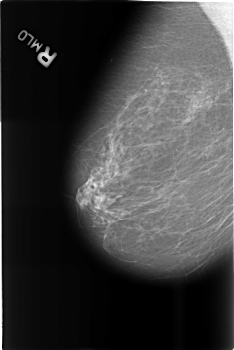

Digital Database for Screening Mammography

Volume: benign_14 Case: B-3467-1

B_3467_1.RIGHT_MLO

DENSITY 2

RIGHT_MLO LINES 4544 PIXELS_PER_LINE 3032 BITS_PER_PIXEL 12 RESOLUTION 50 NON_OVERLAY